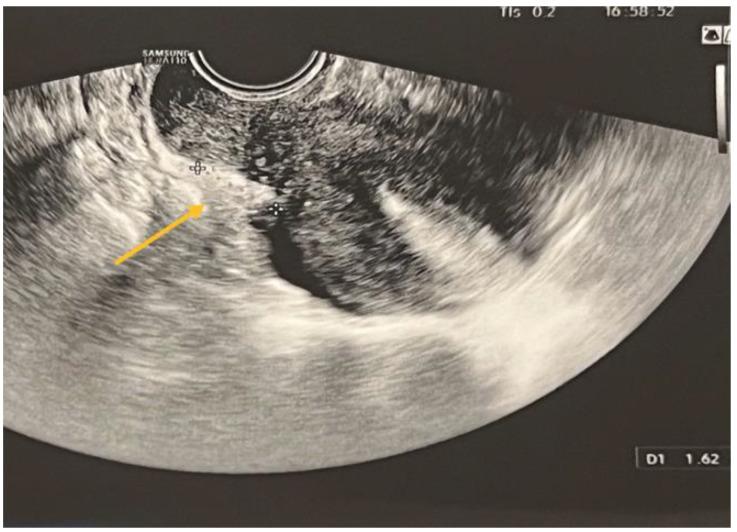

经阴道超声与磁共振成像:诊断子宫内膜异位症的最佳成像方式是什么?

Transvaginal Ultrasound vs. Magnetic Resonance Imaging: What Is the Optimal Imaging Modality for the Diagnosis of Endometriosis?

Endometriosis, an intriguing gynecological illness, poses a substantial health concern for women of reproductive age, despite its widespread occurrence and limited comprehension. The objective of this study is to assess the diagnostic precision of transvaginal sonography (TVS) and pelvic magnetic resonance imaging (MRI) for the identification of deep infiltrated endometriosis (DIE). This study encompassed a cohort of 256 patients exhibiting signs and symptoms of endometriosis, with the aim of assessing the diagnostic accuracy over a span of four years. Both TVS and pelvic MRI were employed in the same centers to analyze each subject. The histopathologic analysis and laparoscopy were the most reliable and widely accepted methods for evaluation. TVS is a reliable diagnostic tool for ovarian endometriomas, obviating the necessity for MRI confirmation. The specificity of TVS in diagnosing ovarian endometriomas is 57.14%, while its sensitivity is 93.78%, resulting in an overall accuracy of 84.47%. In relation to parametrial lesions, the sensitivity, specificity, and accuracy of TVS and MRI were as follows: TVS: 9%, 97%, 32%, MRI: 27.14%, 89.19%, and 40.11%. Concerning the uterosacral lesions, the sensitivity, specificity, and accuracy of TVS and MRI were as follows: TVS:14.63%, 94.74%, and 55%, while MRI: 65.88%, 66.30%, and 66.1%. Regarding rectal endometriosis, the sensitivity, specificity, and accuracy of TVS and MRI were as follows: 69.72%, 76.87%, and 73.82% for TVS, and 66.28%, 94.51%, and 80.79% for MRI. The results of the present study indicate that whereas MRI generally exhibits superior capability in assessing the severity of endometriosis, TVS demonstrates sufficient diagnostic accuracy in DIE comparable to MRI.

摘要

子宫内膜异位症是一种引人关注的妇科疾病,尽管其发病率很高且人们对它的了解有限,但它对育龄女性的健康构成了重大威胁。本研究的目的是评估经阴道超声检查(TVS)和盆腔磁共振成像(MRI)对深部浸润性子宫内膜异位症(DIE)的诊断准确性。本研究纳入了256名有子宫内膜异位症体征和症状的患者,旨在评估四年间的诊断准确性。在同一中心对每位受试者同时采用TVS和盆腔MRI进行分析。组织病理学分析和腹腔镜检查是评估最可靠且被广泛接受的方法。TVS是诊断卵巢子宫内膜异位囊肿的可靠工具,无需MRI确认。TVS诊断卵巢子宫内膜异位囊肿的特异性为57.14%,敏感性为93.78%,总体准确率为84.47%。对于宫旁病变,TVS和MRI的敏感性、特异性和准确率如下:TVS分别为9%、97%、32%;MRI分别为27.14%、89.19%、40.11%。对于子宫骶骨病变,TVS和MRI的敏感性、特异性和准确率如下:TVS分别为14.63%、94.74%、55%;MRI分别为65.88%、66.30%、66.1%。对于直肠子宫内膜异位症,TVS和MRI的敏感性、特异性和准确率如下:TVS分别为69.72%、76.87%、73.82%;MRI分别为66.28%、94.51%、80.79%。本研究结果表明,虽然MRI在评估子宫内膜异位症的严重程度方面通常表现出更强的能力,但TVS在DIE方面显示出与MRI相当的足够诊断准确性。